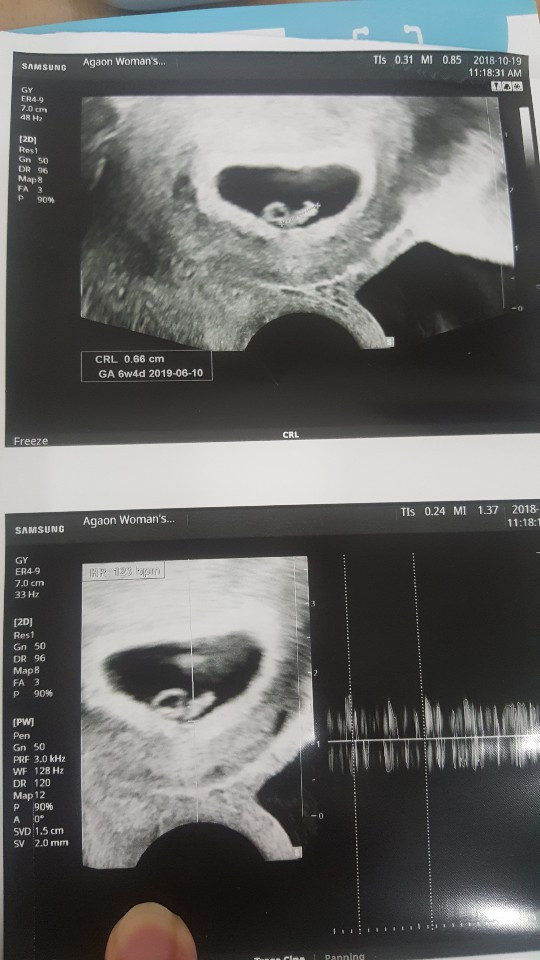

여튼 오늘 방문해서 신랑과 들은 꼬톨이의 심장소리는 규칙적이고 크고 건강했다!

태아들 심장소리가 110-140bpm이 정상범위라는 데 꼬톨이는 130bpm. 너무 좋았다. 눈물이 찔끔났다. 대호와 눈을 마주보고 찡긋 웃었다 :)

2주전에 비해 많이 큰 느낌이다. 이렇게 쑤욱쑥 커서 나중에 사람형태가 되면 너무너무 신기할 것 같아. 꼬톨이가 내 배를 발로 차면 어떤 느낌일까.